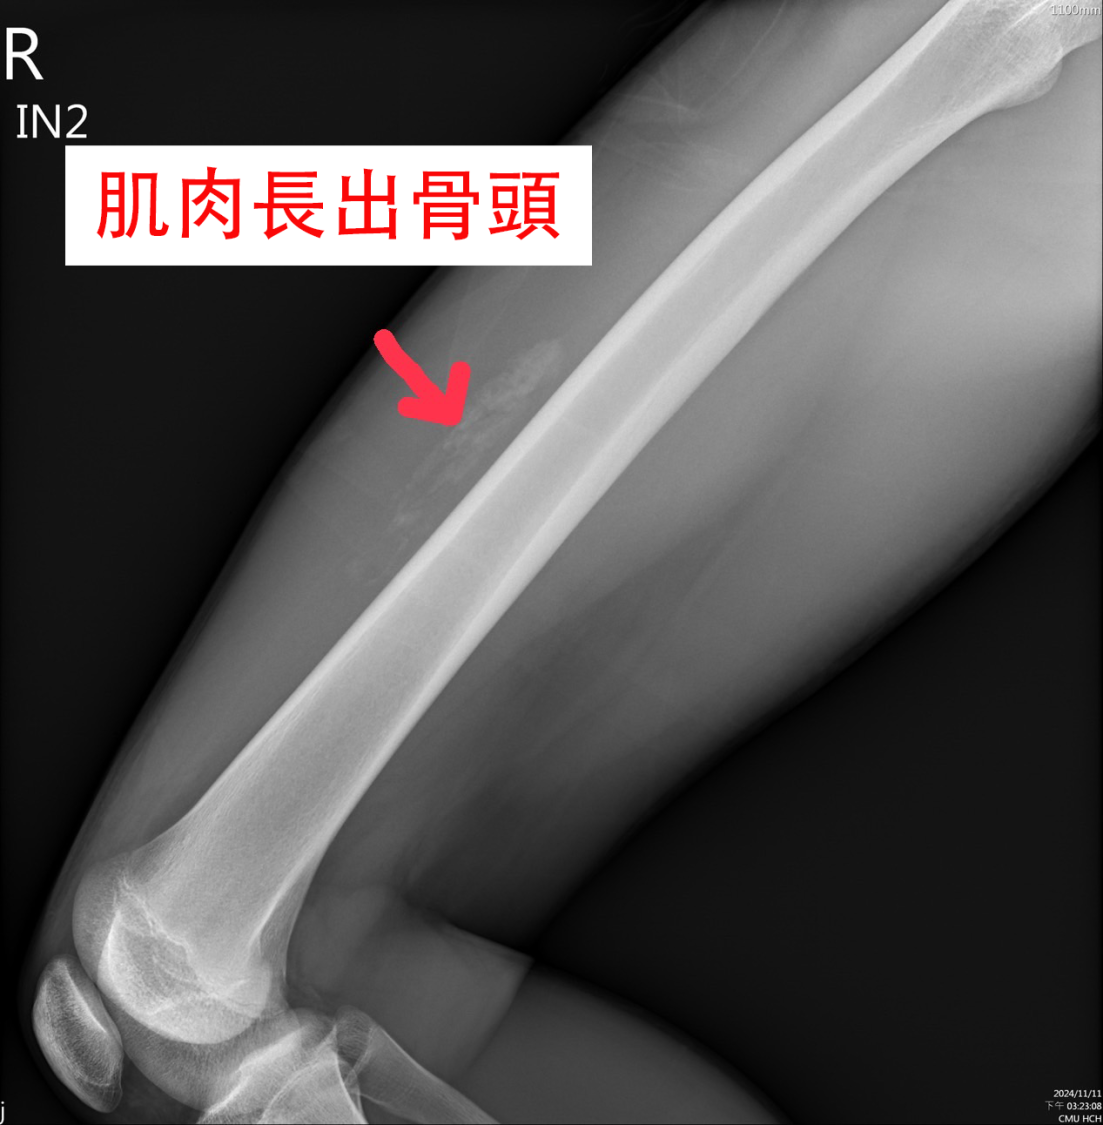

然而,一週後回診檢查,醫師發現該青少年股四頭肌的肌肉中竟然長出了「骨頭」,這正是醫學上所稱的「骨化性肌炎」,是一種由肌肉損傷引起的鈣化性病變,較常見於15至30歲的年輕人。這種情況是因為受傷後,肌肉中的間質細胞過度活躍,形成鈣化組織,類似骨頭的結構。